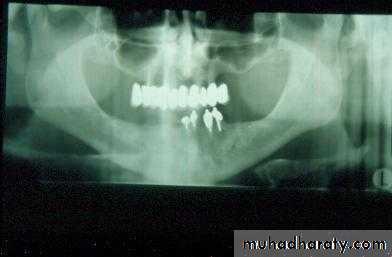

1. Hard tissue2. Soft tissue

1. Hard tissue

a. Dental cariesb. Periodontal disease

c. Infection

d. Cysts and tumours

1. Soft tissue

a. Ulceration

b. Hyperplasia

c. Dysplasia

d. Carcinoma